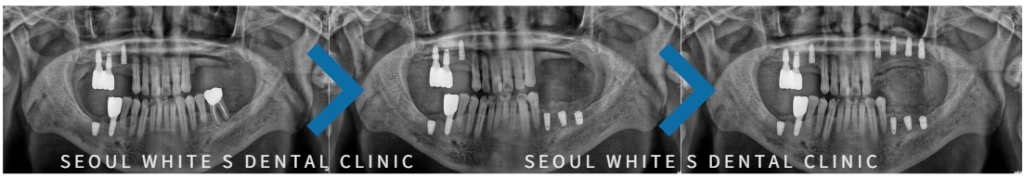

24.10.29 우측 식립/ 25.03.07 좌측 하악 식립/ 25.03.19 좌측 상악 식립

먼저, 우측 임플란트를 2개 식립하고 좌측 아래, 좌측 위 순서로 임플란트를 식립 후 치조골과 단단히 유착될 수 있도록 충분한 시간과 정기적인 확인을 진행하였습니다.

환자분의 걱정과 불편함을 고려하여 급하지않게 차근차근 시간적 여유를 가지고 진행해드렸는데요. 환자분께서 더욱 이러한 세심한 진료과정에 만족해하셨어요:)